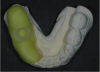

Fig. 16 through Fig. 18 The CEREC Guide was made in the office from a thermoplastic material (yellow). Initially, a radiographic insert (white) was embedded and placed in the mouth during the CBCT scan. After the implant was planned, a drill guide (clear) was milled and inserted into thermoplastic housing. The guide was ready for surgery.